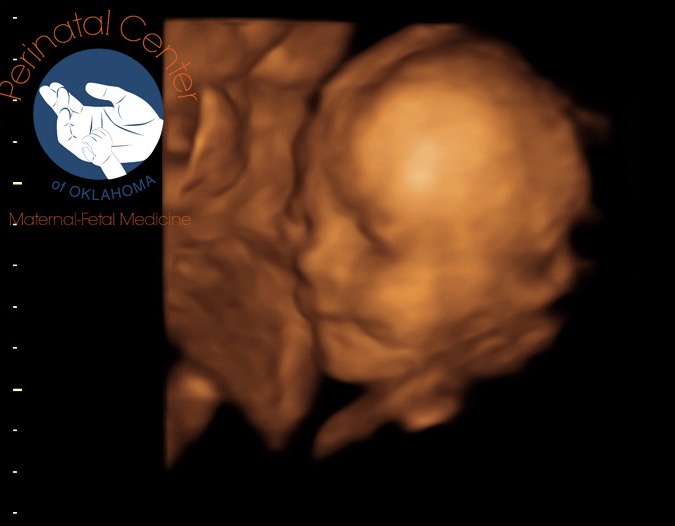

She came as a surprise to us all and has filled our lives with joy and “firsts”, even though she is our third baby. Since my doctors think that I have an autoimmune disease called Sjogren’s that can affect any baby’s heart that I carry, I had to do multiple ultrasounds of the princess during pregnancy. I lost track of how may we did, all in Oklahoma City, which is a 3 hour round trip, but I’m guessing we got to see her little body at least 12 times. The trips were sometimes a pain, but getting to watch her grow was something I hope I never forget. Considering we had just a couple of ultrasounds with our other two kids, this was a new and exciting experience for us.